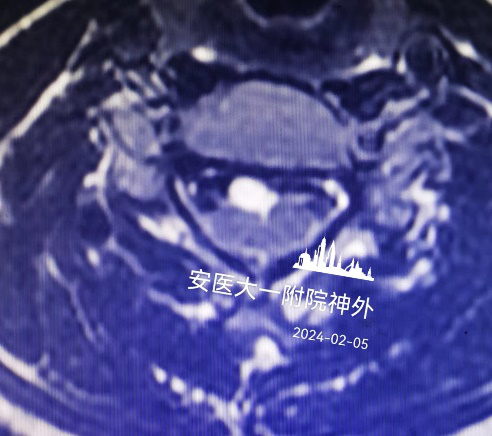

该患者系“右上肢麻木伴左下肢疼痛半年”入院,术前颈椎MR提示C5-6水平脊髓前方囊性占位(图1),囊肿的基底部位于前正中裂至中央管内(图2)。经科室讨论,采用显微镜下颈前经椎体入路脊髓内肠源性囊肿切除术。术后第四天复查磁共振见囊肿全切,无残留(图3),术后颈椎X线片显示内固定位置良好,颈椎曲度理想(图4.5)。术后患者恢复良好,术后第四天患者自己可以下床行走,四肢肌力正常(图6),右上肢麻木稍减退,左下肢疼痛感消失。

图2:脊髓明显受压,肿瘤长入中央管内